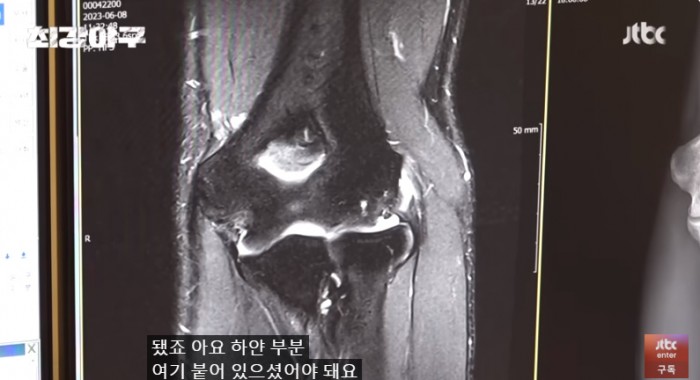

이택근이 팔 통증이 너무 심해 수술 후 타격까지 1년이 걸리는 수술을 했는데..

자신의 자리는 자신이 만들어가는 것이라는 걸 보여준 이택근의 간절함